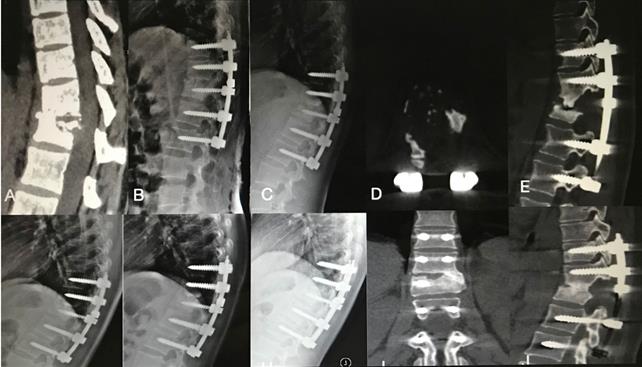

Figure 2

An 22-year-old female patient with thoracic spinal tuberculosis (T11-12) underwent posterior debridement and decompression combined with instrumentation. (A) Preoperative computed tomography (CT) showing bone destruction of the T11-12 vertebrae and compression of the spinal cord. (B,C,D,E) 1-week and 6-month postoperative X-rays and 6-month postoperative CT showing maintained correction and the bone wasn't fully healing. (F,G) 1-year and 2-year postoperative X-rays showed kyphosis correction have loss. (H,I,J)At 4.5-year follow-up, plain X-ray, and CT show solid bone fusion.

The thoracic spinal TB was well cured and the bony fusion at a mean time 12.90±3.91 months in group A was longer than that in group B (6.75±1.55 months) and group C (5.52±1.64 months) (P<0.05) (Figures 2 & 3). No significant difference was found at the mean segmental angle, mean intervetebral height of preoperation and final FU among the groups (P>0.05).